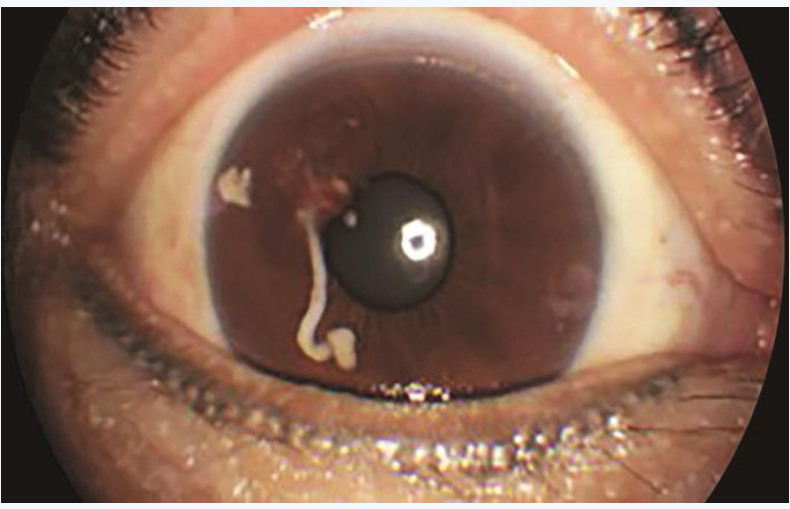

1周后患者复诊,查体:视力右眼0.7,左眼1.0,眼压右眼11mmHg,左眼15mmHg。右眼角膜清,前房中深,瞳孔圆,直径约3mm,对光反射存在,颞上方虹膜实性占位性病变大小未见明显改变,肿物表面出血较前吸收,色素脱失较前加重,前房白色絮状渗出明显吸收(图4)。右眼眼底及左眼查体同前。眼部UBM示右眼颞上方虹膜可见不规则形实性病变,大小约2.88mm×3.80mm×1.90mm,边界尚清晰,内回声不均匀,部分病变与角膜及晶状体前囊相贴,颞侧及下方房角内可见团条状回声,部分与虹膜相连;CDI示右眼颞上方虹膜实性占位性病变大小约3.5mm×2.3mm×1.4mm,边界欠均匀,内回声不均匀,CDFI病变内未探及明显血流信号;眼眶MRI示颞侧虹膜区见条状等T1、略短T2信号影,边缘不清,大小约2mm,增强后可见强化;胸部X线、血尿常规、CRP、生化常规、凝血四项、免疫四项、T-SPOT结核杆菌γ-干扰素释放试验、抗链O、抗核抗体(ANA)、TORCH特异性抗体检查均未见明显异常。

图4 抗炎治疗后右眼前节照相

可见虹膜实性占位性病变大小未见明显改变,肿物表面出血较前吸收,色素脱失较前加重,前房白色絮状渗出明显吸收。